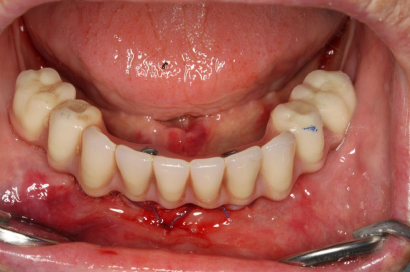

Náhrada jednoho zubu pomocí implantátu je možná také v postranním úseku chrupu. Při ztrátě většího počtu zubů ve frontálním nebo postranním úseku může být mezer uzavřena větším počtem jednotlivých implantátů.

Při ošetření pomocí jednotlivých implantátů zůstávají sousední zuby neporušené – intaktní. Při klasickém ošetření pomocí můstků musejí být tyto zuby obroušeny!